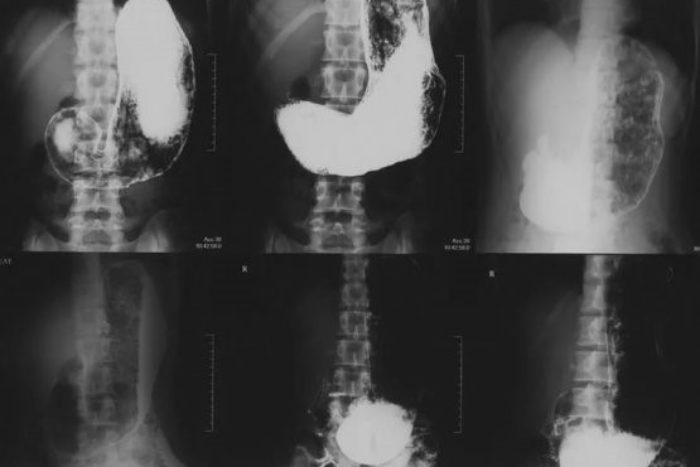

Погибшие пили раствор сульфата бария — он необходим для контрастной рентгенографии

Перед обследованием пациенты пили раствор сульфата бария — это контрастное вещество, позволяющее получить более точные снимки. По данным «Фонтанки», после процедуры погибли 60-летняя женщина и 42-летний мужчина, подробности о третьем погибшем неизвестны.

Сульфат бария повсеместно применяется как рентгеноконтрастное вещество. Он нетоксичен, что отличает его от всех прочих растворимых солей бария — они для человека ядовиты. Для рентгенографического исследования пациент принимает внутрь суспензию сульфата бария с содержанием бария 58,7 %.